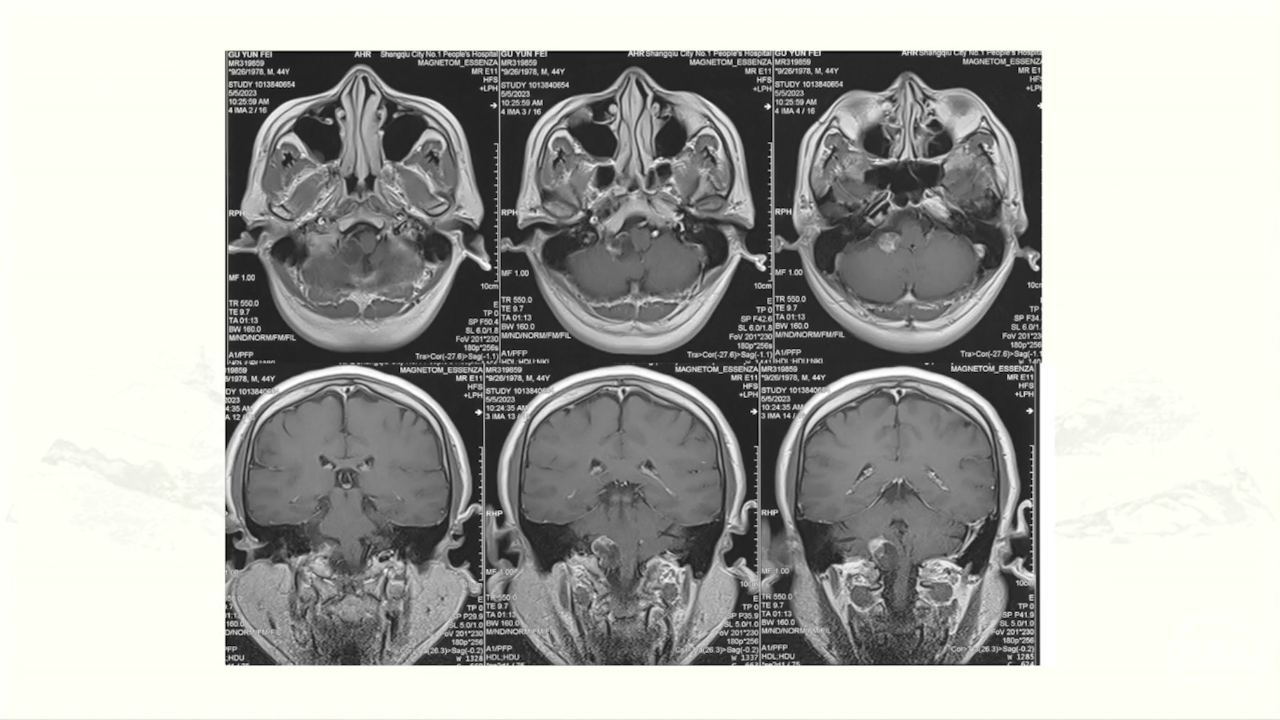

颈静脉孔区肿瘤充分显露是硬道理。肿瘤越大,工作通道越宽。颈静脉孔扩大越明显,开放颈静脉孔越容易。

卜博教授:颈静脉孔区肿瘤:解剖及156例经验